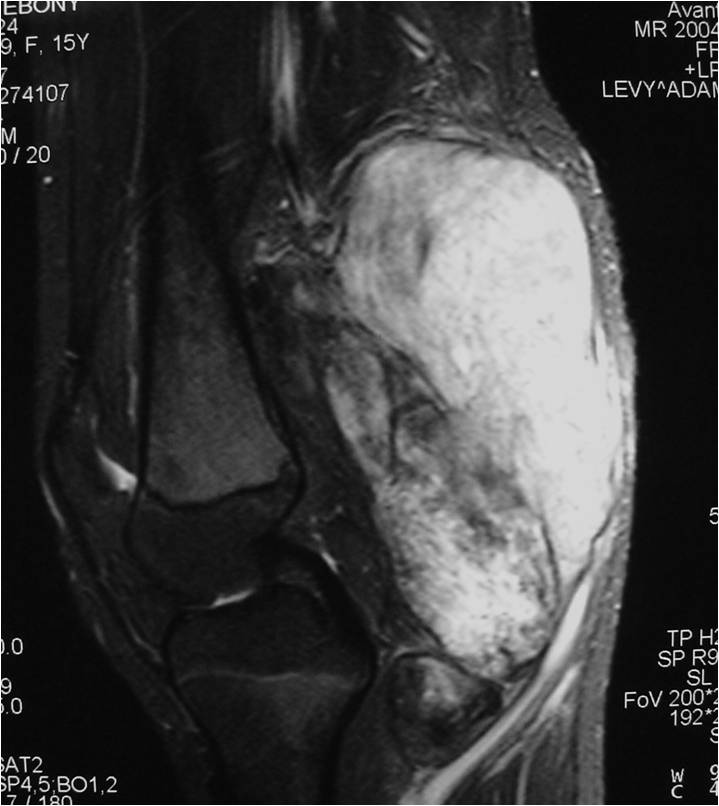

Radiographic Presentation

- Aggressive motheaten to permeative lesion

- Indistinct border in most cases

- Osseous destruction with a soft tissue component

- Chondroid matrix calcification may be present (60-70% of cases)

- Soft tissue mass

- Locally aggressive

- Cortical destruction in approximately half of cases

- Extension of tumor into adjacent soft tissues